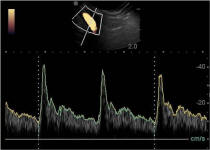

A New 464 Page Textbook, in Full-Color with 630 Pictures and Drawings, by Pete Ramey

A Few Pictures from the book:

Photos referenced in text from Bidwell/Bowker, Bowker, Clayton, Cowles, Hampson, Kellon, Ramey, Ridgway, Sullivan, Taylor, Watts.